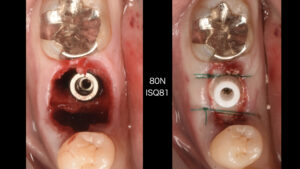

抜歯した穴にインプラントを入れるスペースを形成して、埋入していきます。

適切な位置にインプラントを埋入し、仮歯を作製していきます。

オペが終わりました。当日、インプラントの仮歯に置き換わります。